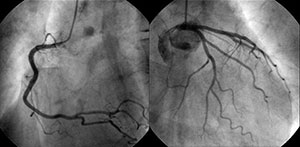

カテーテルで撮影した正常の冠動脈

病気の診断には冠動脈のかたちを直接撮影する冠動脈造影検査(心臓カテーテル検査の一種)が用いられます。 これによって、冠動脈の狭窄の部位や程度を評価して治療方針を決定することが可能です。 また前述した冠攣縮性狭心症の診断のための冠攣縮誘発試験もおこないます。